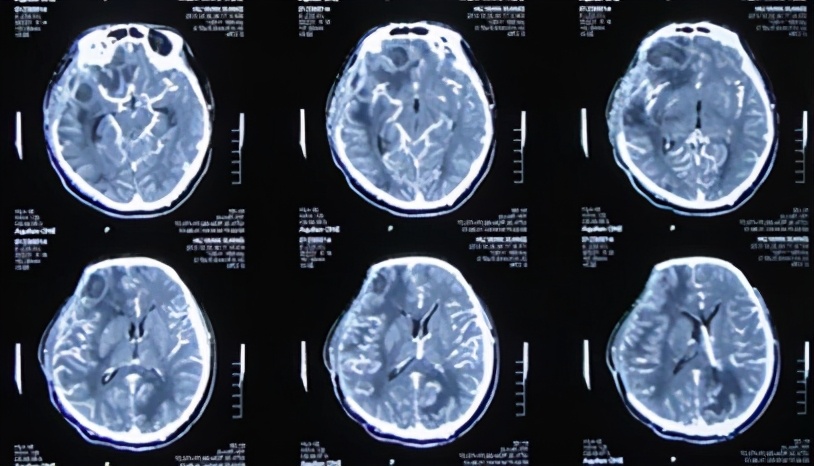

2013年10月1日即开颅术后第14天转来,入院时:意识模糊,躁动,右侧额颞顶减压窗张力高,手术切口感染、敞开,长约14cm,深达颅内,可见部分脑组织暴露,切口边缘可见脓苔,切口周围头皮苍白;左顶部见直径约2.5cm头皮缺损,深达颅骨,周围可见脓胎(图-5)。查头CT:右侧开颅区部分脑组织疝出(图-6)。

图-5:2013年10月1日入院时

图-6:2013年10月1日头CT

当天立即急诊进行了左侧侧脑室引流减压及切口清创和转移皮瓣缝合术(注:缩小脑外露的范围)(图-7)。术后当日复查头CT:脑室引流术后改变(图-8)。

图-7:2013年10月1日术后

图-8:2013年10月1日术后头CT

2013年10月5日即入院术后第4天(开颅术后第18天),复查头CT:脑肿胀及脑膨出均减轻(图-9)。

图-9:2013年10月5日头CT

于2013年10月7日即入院术后第6天(开颅术后第20天),再次复查头CT显示脑肿胀及脑膜脑膨出继续减轻(图-10)。并当天给予行右颞部原伤口的二次缝合术(注:彻底封闭了脑外露)(图-11)。

图-10:2013年10月7日头CT

图-11:2013年10月7日完全封闭脑外露

2013年10月13日即入院术后第12天(开颅术后第26天),再次复查头CT:脑肿胀及脑膨出进一步减轻(图-12)。

图-12:2013年10月13日头CT